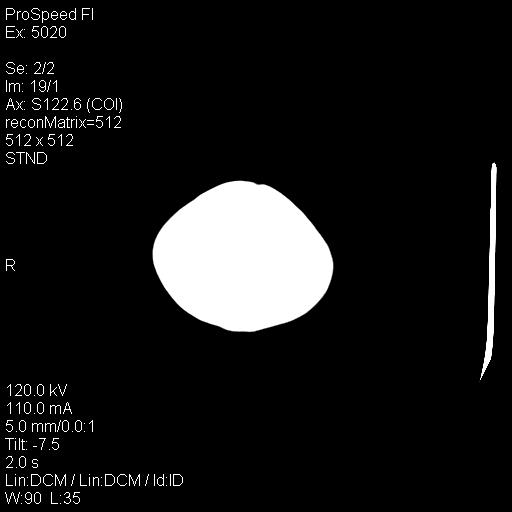

标题: PED1637:M 6Y 顶部无痛性包块两月。 [打印本页]

标题: PED1637:M 6Y 顶部无痛性包块两月。

2、颅骨局部缺失,边缘光滑、整齐

颅骨的病损表现为内外颅骨板层不规则的锋利的破坏,形成“斜边缘”,有一定的特点

颅骨为好发部位,生长缓慢,常位于顶骨、枕骨及颞骨,表现为颅骨缺损,呈圆形或椭圆形,边界清,无硬化

事发冠状缝与矢状缝交界区,密度较低,考虑表皮样囊肿可能性大,其次不除外嗜酸性肉芽肿